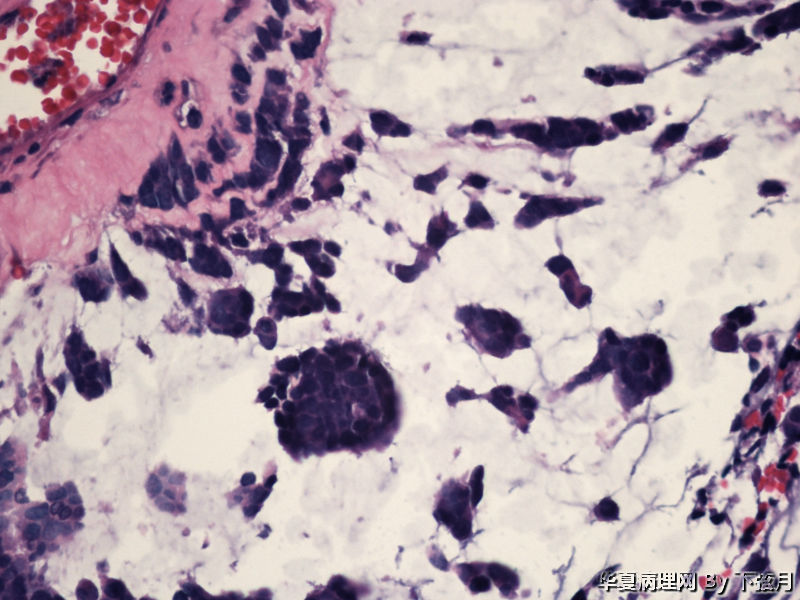

左侧颞叶及胼胝体膝部占位图8

名称:图8

描述:HE 400倍-3

This enhancing lesion with GFAP positive cells and should consider some type of glioma, probably high-grade.

But some cells in fig 7 and 8 are worrisome, need to rule out other type tumors, like chordoma. Other small round blue cell tumors.

丰富黏液背景,漂浮乳头状或簇状分布的瘤细胞,免疫组化GFAP,S-100阳性。

有血管轴乳头,粘液样物中漂浮的细胞呈团块状和小乳头状。支持粘液型乳头状室管膜瘤。